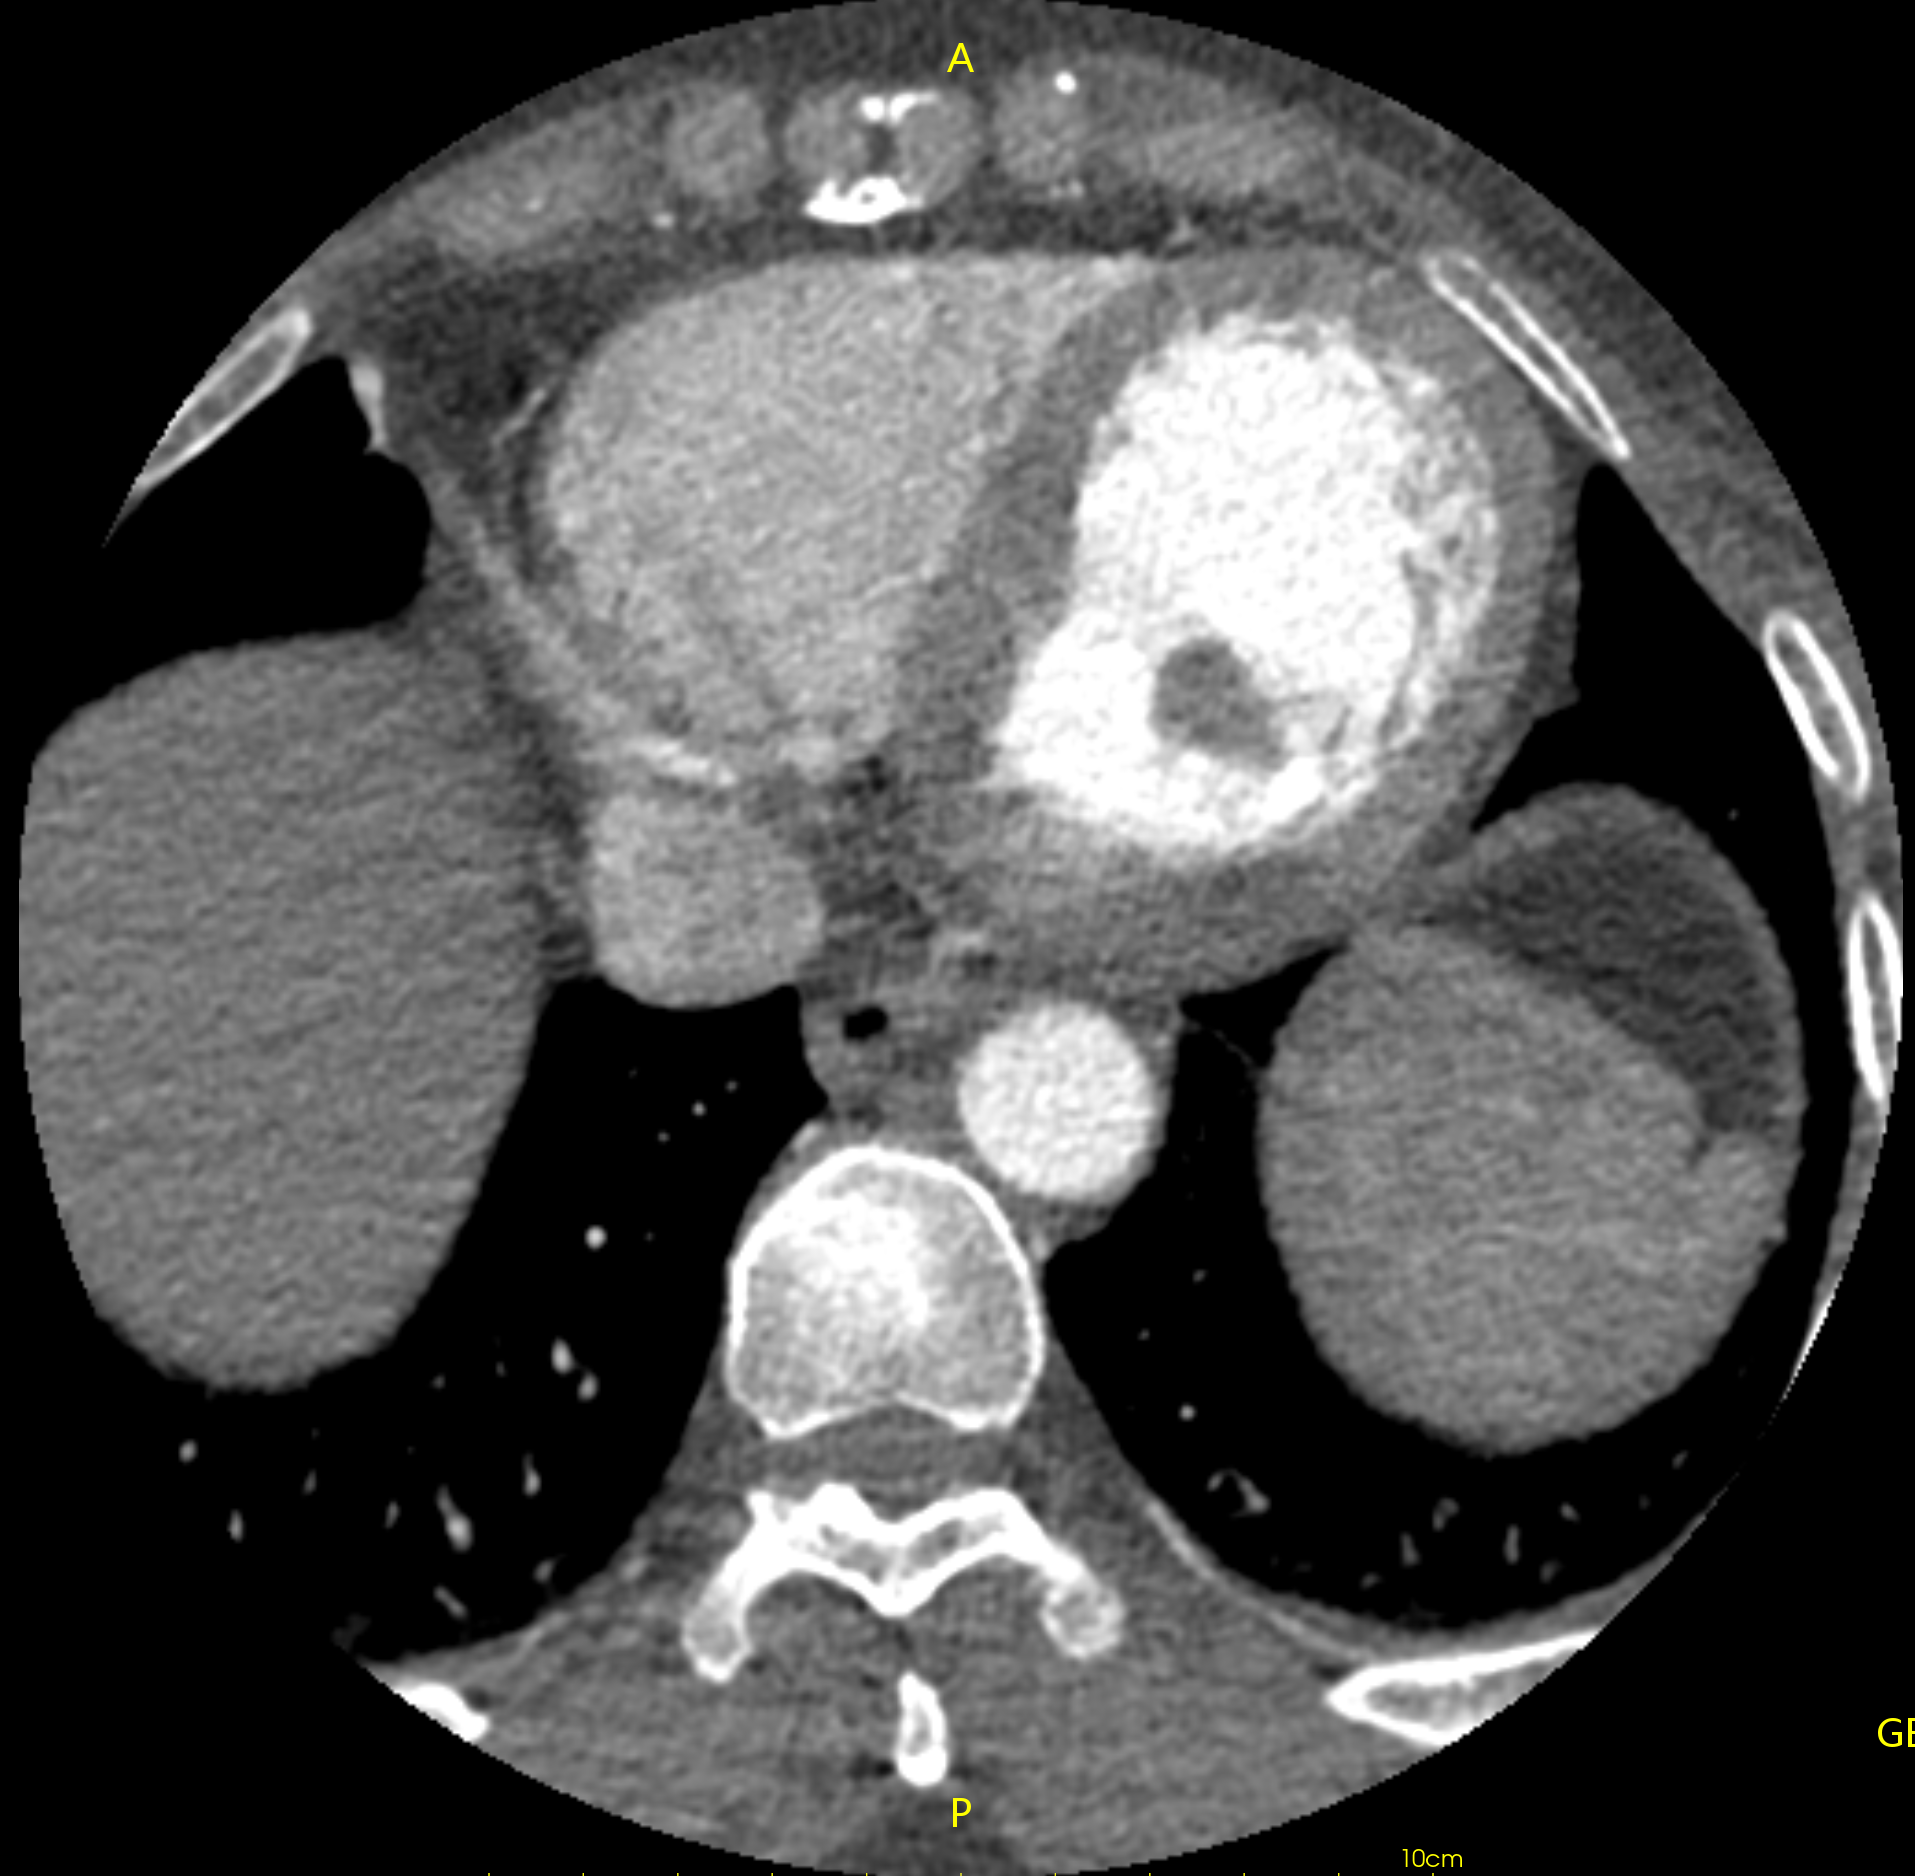

https://blog.csdn.net/liushao1031177/article/details/117696381 如果遇到下面这种有明显边界的ct影像,如何才能区分哪些是有效的CT值,哪些是背景值?

我们可以根据0028,0103内值来区分图像是否被填充过,如果pixel representation为0,则该CT图像未被填充过,其内部像素值都表示有效CT数值;如果pixel representation为1,则该CT图像内有两部分CT值,一部分是有效CT值,另一部分是填充值,只是为了把图像展示成矩形图像;

我遇到的这个数据中,0028,0103为1,则存在0028,0120值,其值为-2000。

我遇到的这个数据中,0028,0103为1,则存在0028,0120值,其值为-2000。

由于图像的斜率为1.0,截距为-1024,则-2000就会在线性变换后为-3024;

找一个背景值,可以看到该值为-3024;则像素值为-3024的像素即为填充像素,可以在后处理中过滤掉;